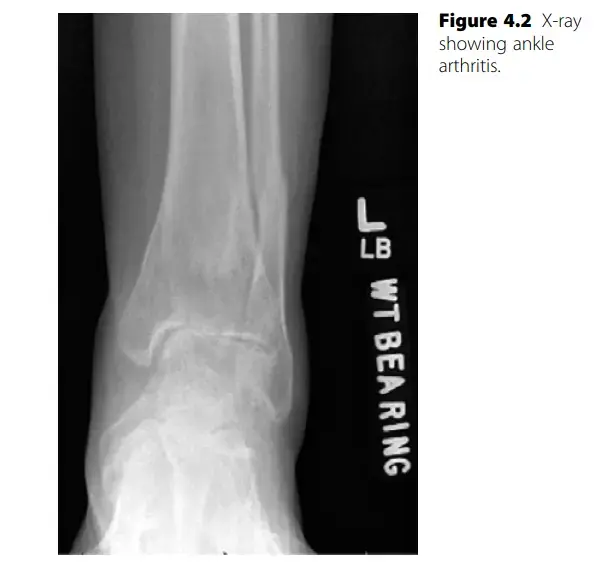

3. الأشعة السينية (X-rays): تُعد الأشعة السينية هي الاختبار التصويري الأول والأكثر أهمية. تظهر الأشعة تضييق المسافة المفصلية (مؤشراً على تآكل الغضروف)، وجود نتوءات عظمية، وتغيرات في بنية العظام. يمكن أن تُظهر الأشعة أيضاً علامات على كسور قديمة أو تشوهات.